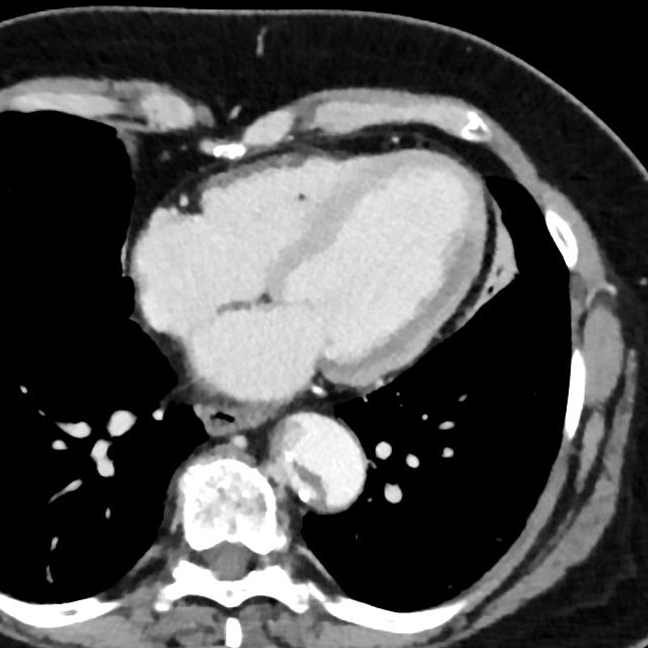

60 year old female presented to the hospital with chest pain. Venous phase CT shows a subtle area of decreased perfusion in the left ventricle. This is much more obvious on monoE images, and of course stands out on the iodine map and the Z-eff images. The arterial phase image shows the Stanford type A dissection, and involvement of the left main coronary artery.

Conventional CT, venous phase. You might pick up hypoperfusion in lateral wall of left ventricle on a good day, but then again…